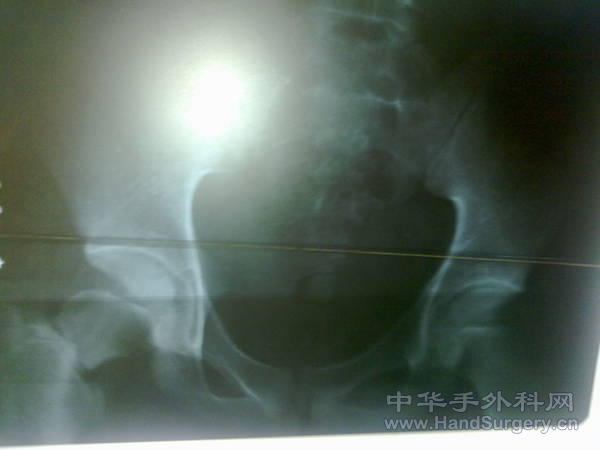

发一例股骨颈骨折

患者17岁,外伤致股骨颈骨折,请大家看看是否有更好的固定方法。